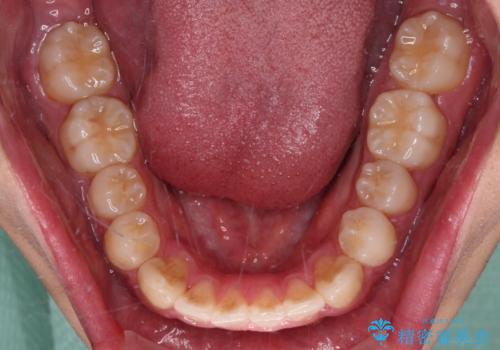

インビザライン・ライトは、製作できるアライナーの枚数に制限があるため、移動可能な量に限りがあります。

一方で、半年から1年程度で治療を終えることができるため、軽度の歯列不正の患者様には大変お勧めです。